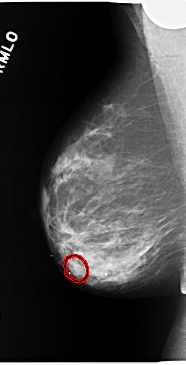

C_0168_1.RIGHT_MLO

RIGHT_MLO LINES 5840 PIXELS_PER_LINE 2976 BITS_PER_PIXEL 12 RESOLUTION 50 OVERLAY

FILE: C_0168_1.RIGHT_MLO.OVERLAY

TOTAL_ABNORMALITIES 1

ABNORMALITY 1

LESION_TYPE MASS SHAPE OVAL MARGINS OBSCURED

ASSESSMENT 4

SUBTLETY 3

PATHOLOGY MALIGNANT

TOTAL_OUTLINES 1

BOUNDARY